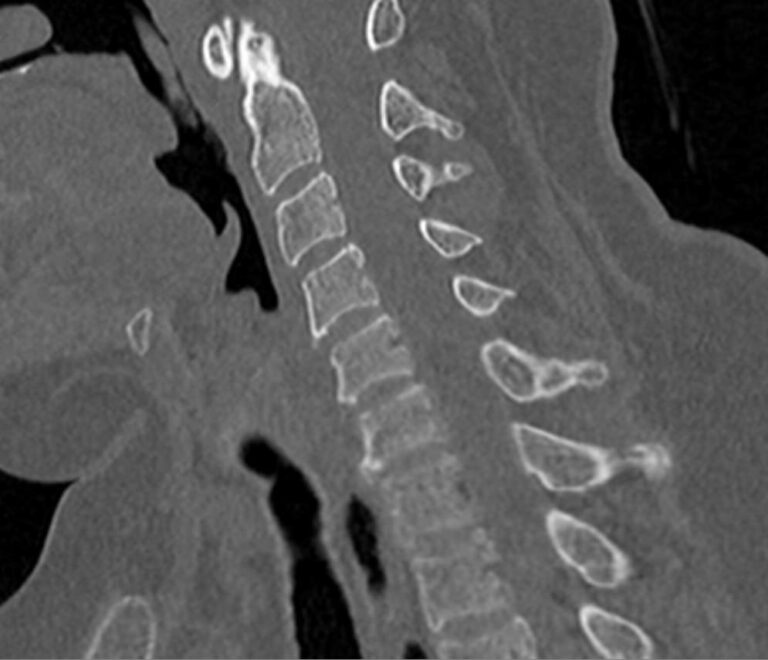

Мультиспиральная компьютерная томография (МСКТ) является современным, высокоинформативным методом диагностики различной патологии позвоночного столба. Благодаря МСКТ можно визуализировать костную структуру позвонков, выявить воспалительные, дегенеративные и опухолевые процессы на исследуемом уровне. В основе метода лежит использование ионизирующего излучения и способность различных тканей по-разному поглощать рентгеновские лучи.

В нашей клинике КТ двух отделов позвоночника проводится на новейших мультиспиральных томографах экспертного уровня TOSHIBA AQUILION (64-срезовый и 128-срезовый). Сканеры производят тончайшие срезы исследуемой зоны толщиной от 0,5 мм и позволяют визуализировать костные структуры позвоночника с высокой детализацией. Увеличенное количество высокочувствительных детекторов аппаратов обеспечивает высокую разрешающую способность и четкость изображений, при этом позволяет выполнить исследование в течение нескольких секунд с минимальной дозой облучения.

Инновационные возможности мультиспиральных томографов, которыми оснащены наши медицинские центры, позволяют создавать 3D-модели позвоночника на рассматриваемом уровне для более точной локализации очага и оценки взаимного расположения органов и тканей.